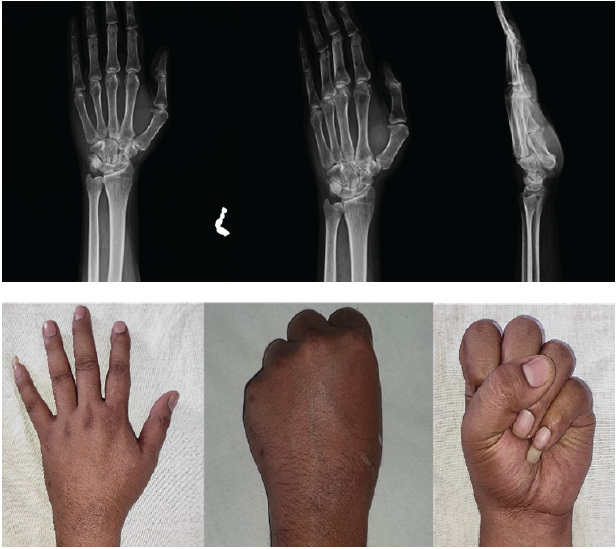

Dynamic fluoroscopy showed stable fixation and reduction. Postoperatively, a cock-up splint was applied, and immobilization was continued for 6 weeks. K-wires were removed after 6 weeks. Satisfactory reduction was maintained on re-examination after 6 weeks following cast removal (Fig. 5).

Figure 5: A series of photographs showing radiographs and clinical pictures at 6 weeks when the K-wires were removed. The patient had no to very little movement at the carpometacarpal joints at this stage.

Physiotherapy was started 6 weeks postoperatively after K-wire removal with active and passive mobilization of the wrist joint, metacarpophalangeal joints, and proximal and distal interphalangeal joints of fingers, to achieve good functional recovery. Full range of motion of the hand was achieved, showing a good result at 1-year follow-up (Fig. 6).

Figure 6: A series of photographs showing the radiographs and excellent clinical outcome of the patient at 1-year follow-up.